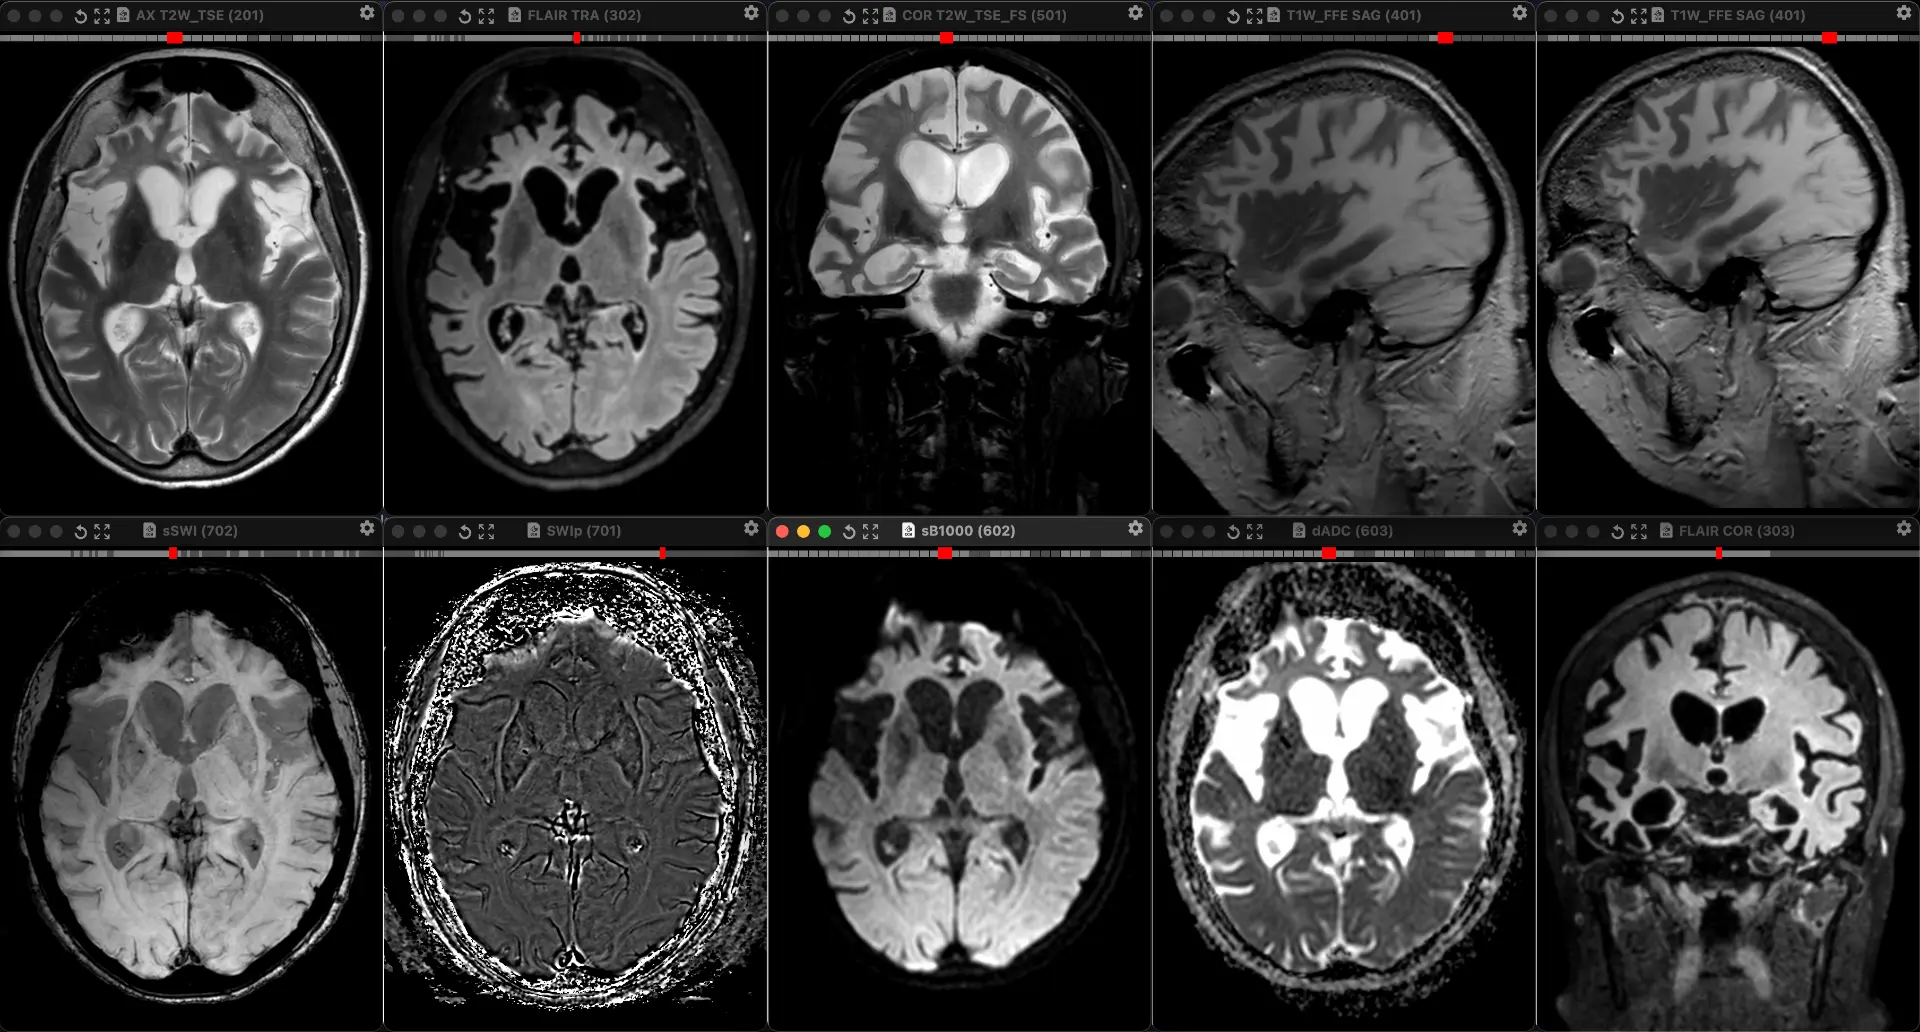

Женщина 32 года. Больной считает себя с 2024 г, когда стала отмечать онемение угла рта. Со слов пациентки ей был предварительно выставлен диагноз - РС, но дополнительных методов обследования и специфического лечения не проводилось. В настоящее время жалоб нет. В исследовании от октября 2024 отмечался очаг в левой затылочной доле с выраженным контрастированием, в настоящее время этот же очаг отмечается с сохраняющимся контрастированием. Формально - есть выполнение критериев диссеминации и в пространстве (юкстакортикальный и перивентрикулярный очаги есть), и во времени (есть усиливающиеся и неусиливающиеся очаги), клиника тоже вполне укладывается. Но! Найти в литературе подобных случаев мне не удалось, видел сам и максимум, что находил в литературе - полгода контрастирования. Получается, мы имеем дело с крайне атипичным рассеянным склерозом, или это не рассеянный склероз. А тогда что? Сосудистая мальформация не вариант - на SWI не видать. Какая-то ганглиоглиома? А другие очаги тогда что? Есть соображения? Кстати, диффузия стойко повышенная, и на б1000 почти не видно (изо). На Т2 не меняется